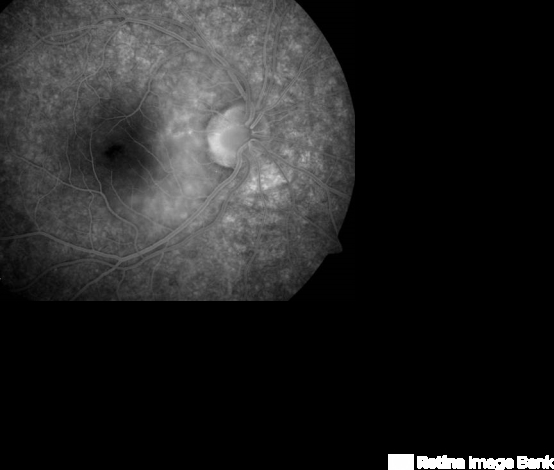

- optic pit

- Late phase FA of a young patient with optic pit.